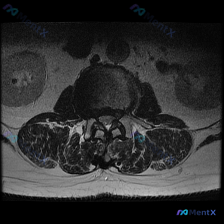

看到这张腰椎MRI T2轴位片,整理一下完整的分析思路分享给大家。 病例基础信息 这是一例腰椎MRI T2序列轴位影像,定位为下腰椎节段(L4/5或L5/S1,需结合矢状位确认),影像清晰显示椎体、椎间盘、椎管、硬膜囊、马尾神经、黄韧带、双侧关节突关节及椎旁肌肉结构。 核心影像发现 1. 椎间盘改变...

腰椎MRI轴位读片分享 今天拿到这个腰椎轴位T2加权MRI,正好整理一下读片和分析思路,分享给大家。 --- 病例影像基础信息 提供的是腰椎MRI T2加权轴位影像,没有侧位定位像和矢状位序列,我们先基于现有信息分析: 1. 定位:从椎体形态、关节突位置、硬膜囊结构来看,这个层面大概是L4/L5或者...